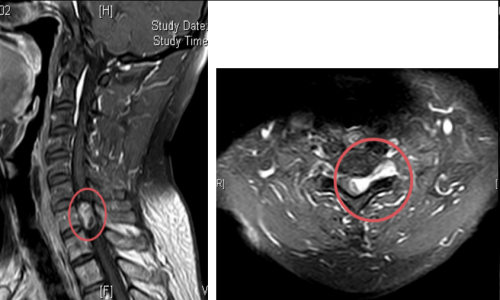

术前核磁检查颈胸段椎管内存在占位性病变,且脊髓已被挤压成线形

若不尽快手术切除肿瘤,随着肿瘤持续增大,脊髓受压程度会不断加重,进而造成不可逆的神经损伤,最终甚至可能导致四肢瘫痪。接下来,脊柱外科一区主任、主任医师许宇霞带领团队成功为张淮实施了高难度颈胸段椎管内肿瘤切除术。术中快速病检提示肿块为“神经鞘瘤”,这类肿瘤多为良性肿瘤,手术切除后预后良好,复发率低。术后张淮恢复良好,原有颈肩疼痛消失,左上肢麻木无力及右下肢行走无力等症状均显著改善。